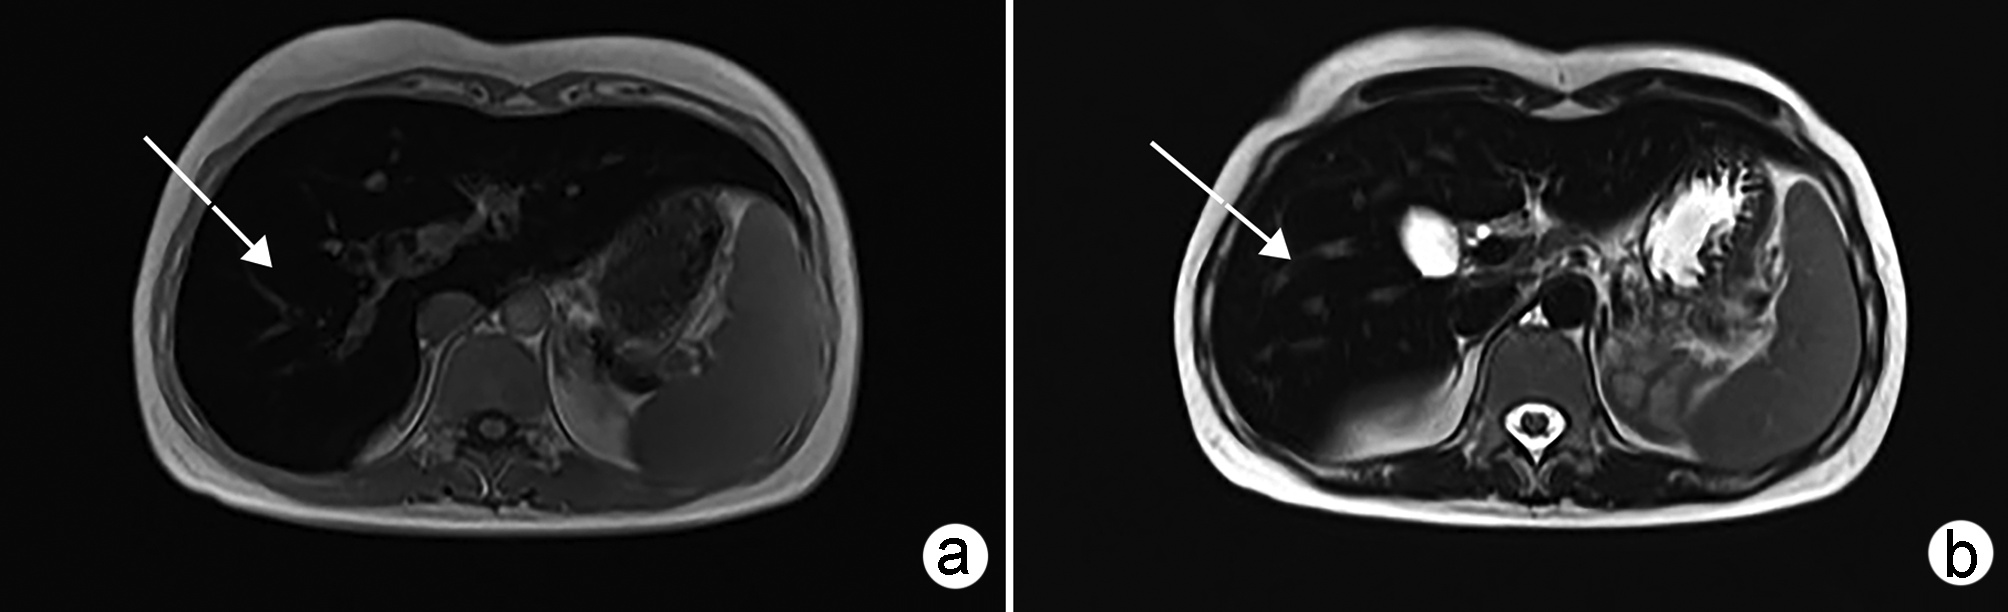

吲哚菁绿荧光显影在困难胆囊腹腔镜胆囊切除术中的应用价值

摘要:

目的  探讨吲哚菁绿(ICG)荧光显影在困难胆囊腹腔镜胆囊切除术(LC)中的应用价值。  方法  回顾性分析安徽医科大学第一附属医院2021年10月—12月行LC的患者临床资料,根据术中是否使用ICG荧光显影和是否为困难胆囊分为4组:A组为使用ICG荧光显影普通胆囊,B组为使用ICG荧光显影困难胆囊,C组为未使用ICG荧光显影普通胆囊,D组为未使用ICG荧光显影困难胆囊。比较各组手术时间、术中出血、住院时间、住院费用和术后并发症间的差异。正态分布的计量资料2组间比较采用t检验。计数资料2组间比较用χ2检验或Fisher确切概率法。  结果  A组与C组相比手术时间、术中出血、住院时间、住院费用和术中并发症,差异均无统计学意义(P值均>0.05)。B组手术时间和术中出血分别为(75.41±12.96)min和(18.27±6.97)mL,D组分别为(106.78±19.21)min和(23.99±8.43)mL,两组相比差异均有统计学意义(P值均<0.05);B组住院时间、住院费用和术后并发症与D组相比,差异均无统计学意义(P值均>0.05)。  结论  普通胆囊患者LC术中使用ICG荧光显影优势不明显;但在困难胆囊中,ICG荧光显影有利于胆道显露,可以缩短手术时间,减少术中出血。ZHANG Chao